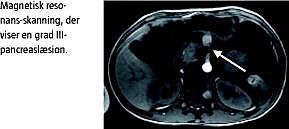

En niårig dreng kørte med gokart ind i et rækværk og fik rattet i maven. Han blev set i skadestuen og blev sendt hjem. I hjemmet havde patienten opkastninger og var utilpas og blev efterfølgende indlagt på et lokalt sygehus. Objektivt fandt man direkte ømhed i øvre abdomen. Biokemisk fandt man amylase på 1.198 U/l. Ultralyd af abdomen viste fri væske intraabdominalt, og ved computertomografi (CT) af abdomen fandt man læsion af pancreas. Patienten blev efterfølgende overflyttet til en specialafdeling. Der blev foretaget magnetisk resonans-kolangiopankreatikografi (MRCP), som viste en grad III-pancreaslæsion. Patienten blev behandlet nonoperativt og fik normal enteral ernæring. Klinisk fik patienten det gradvist bedre. Kontrolultralydsskanning af abdomen 11 dage efter traumet viste en pancreaspseudocyste på tre centimeter. Patienten blev udskrevet i velbefindende 12 dage efter traumet. Pseudocysten i pancreas var forsvundet ved kontrolultralydsskanning en måned efter traumet. Biokemisk normaliseredes amylasen først to måneder efter traumet, hvor patienten var velbefindende.